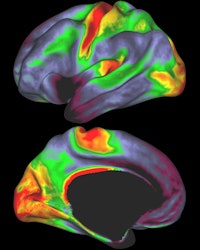

Red and yellow indicate regions with high myelin levels, while blue, purple, and black areas have low myelin levels. Image courtesy of David Van Essen, PhD.

Study co-author David Van Essen, PhD, head of the department of anatomy and neurobiology at Washington University, said the myelin maps will provide important insight into where certain parts of the brain end and others begin.

Access to detailed myelination maps in humans and animals will also help efforts to understand how the brain evolved and how it functions.